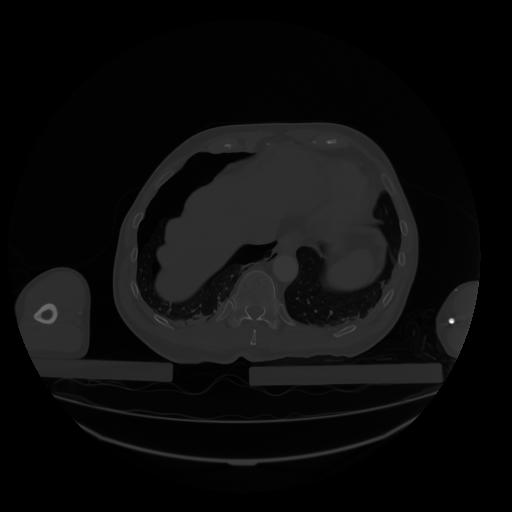

28 CUERPO,CE,Vol,2.0,CUERPO,,